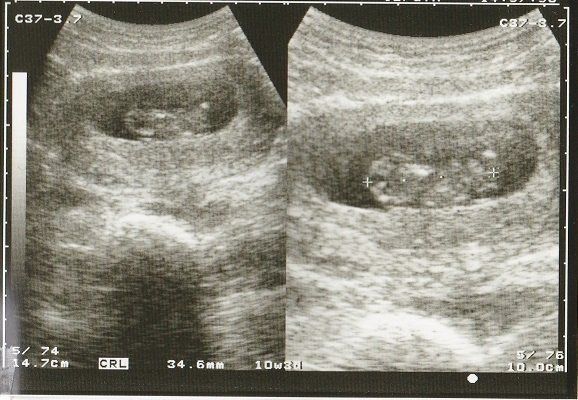

妊娠10週目のエコー写真 大きな塊に

まだまだ「赤ちゃんだなあ」とは思えない形の画像です。